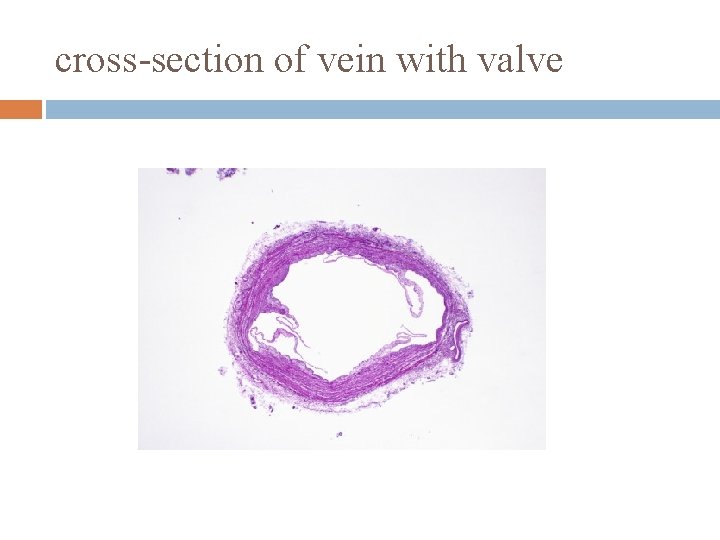

cross-section of vein with valve